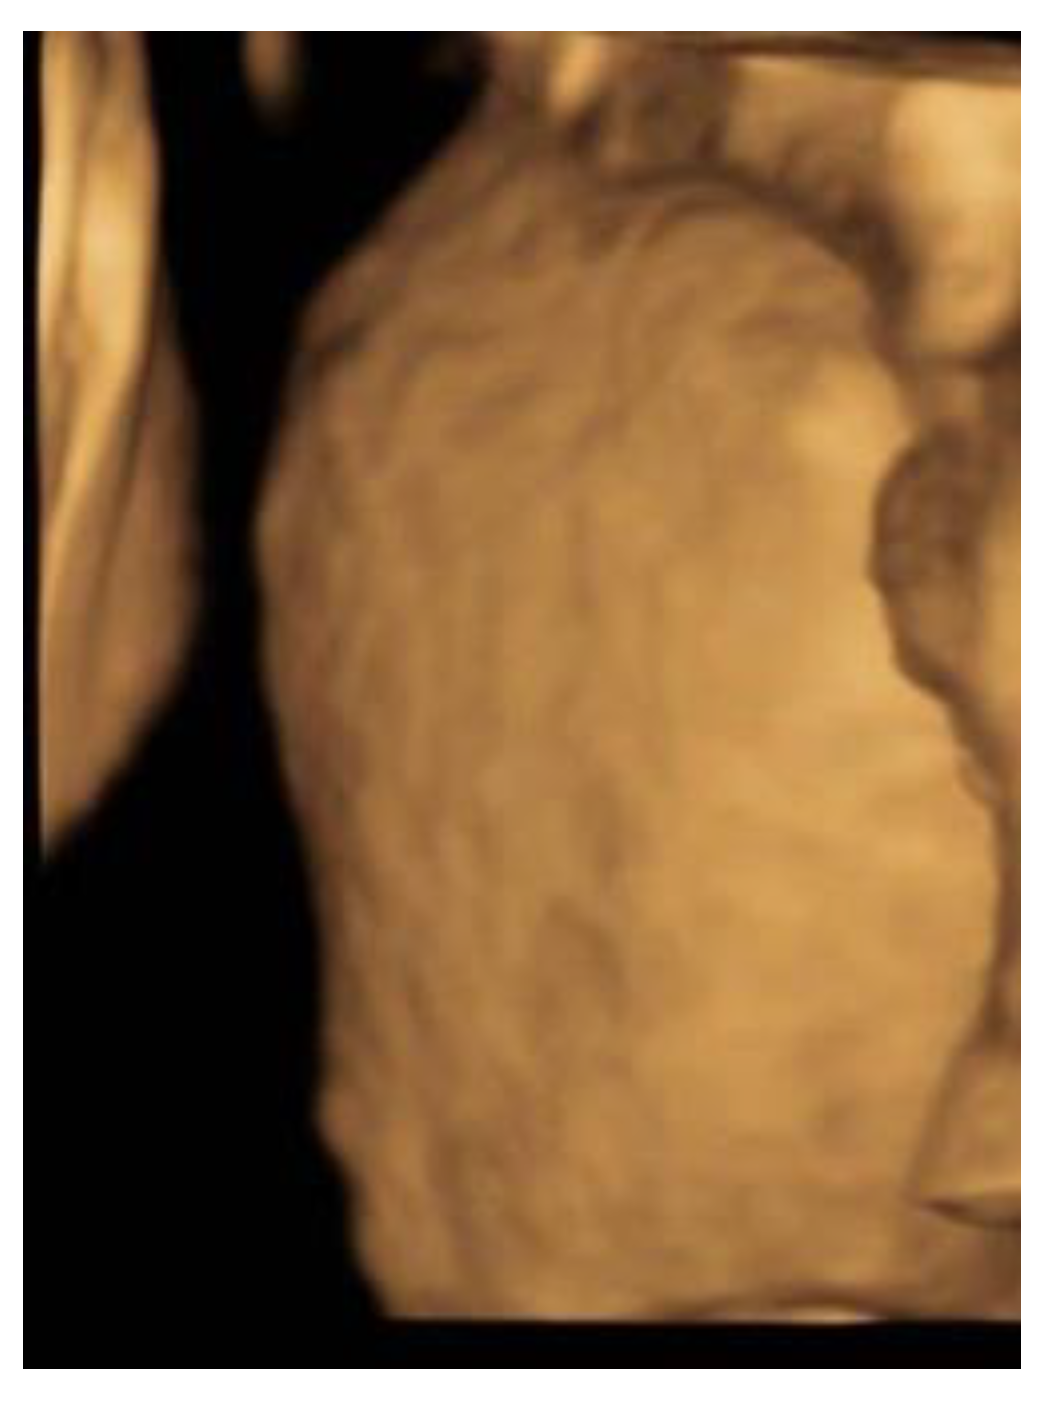

Figure 1), but no distinct banana-sign. Inspection of the spine was inconspicuous. The patient was reevaluated in our center at 24 weeks GA. The hydronephrosis of the upper pole of the left kidney remained stable. However, the cerebellum presented a banana-shape with herniation of the hindbrain onto C2 and minimal lemon-sign of the skull (

Figure 2). The lateral ventricles were not dilated. Ultrasound examination of the spine revealed a closed skin except for a minimal fistula in the sacro-coccygeal region (